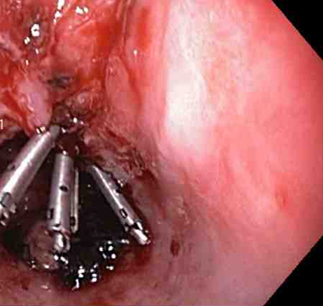

Laceração de Mallory-Weiss

Três clipes tipo "through-the-scope" para o fechamento completo do defeito na mucosa

Do acervo de Juan Carlos Munoz, MD, University of Florida